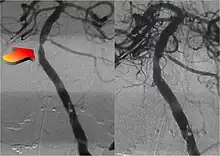

Parallel to the development of catheters, in the radiology and neuroradiology units, image technology dramatically improved: Charles Mistretta in 1979 invented digital subtraction angiography (DSA), the technique currently in use. It consists of performing skull radiography under basic conditions which are then "subtracted" to the image after contrast media injection, to provide an image where only brain vessels are displayed, with great improvement in the diagnostic potential.